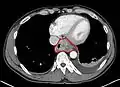

إن أفضل الطرق لتشخيص المرض هي عن طريق التنظير الباطن العلوي حيث يمكن رؤية الورم بشكل مباشر وأخذ خزعات من المناطق المصابة وفحصها مخبرياً، كما يمكن استخدام عدة فحوصات شعاعية للمساعدة في تشخيص المرض وتحديد مدى تغلغل الورم وانتشاره، من أهم تلك التقنيات: التصوير الطبقي المحوري و وجبة الباريوم, وقد يتم إجراء اختبار حركية المريء لاستبيان تضرر عضلات المريء بسبب السرطان.

معرض صور